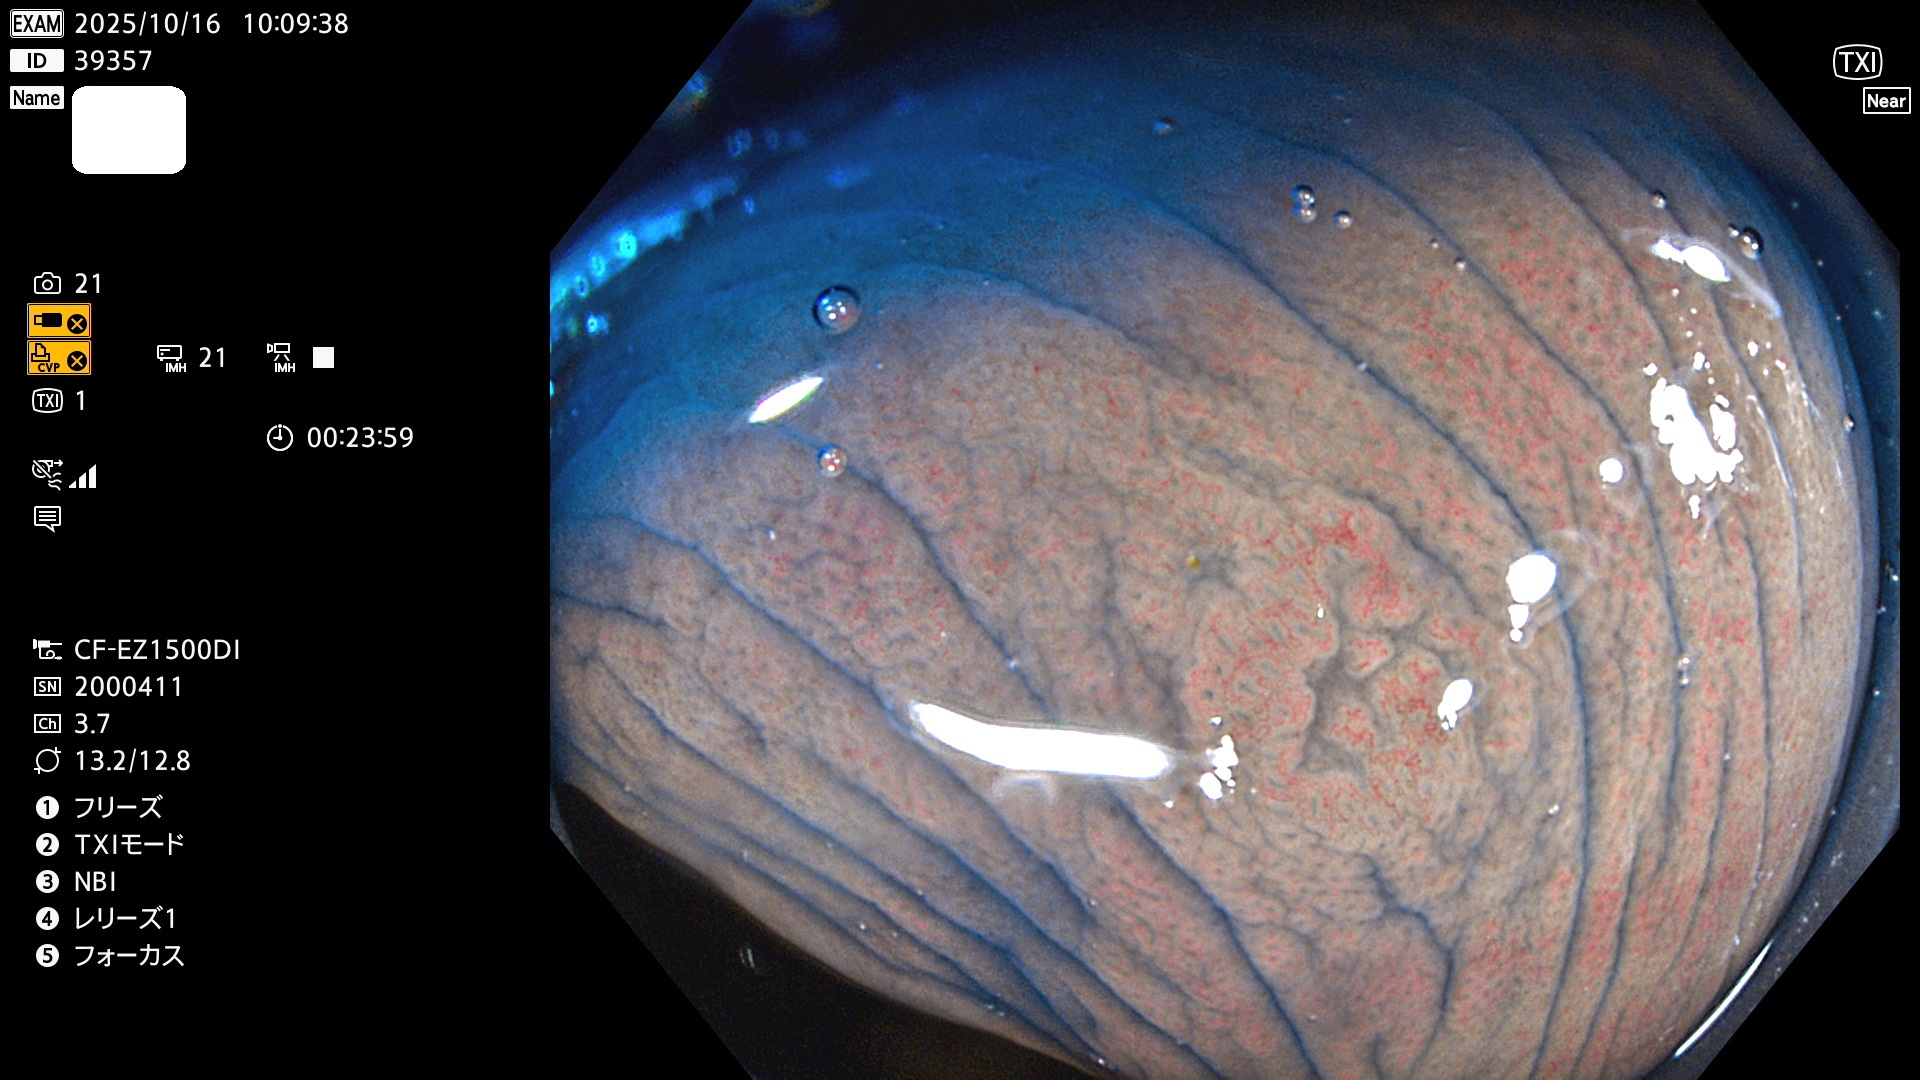

完全に平坦な物をUb、陥凹している物をUcと呼びます。Ubは認識が困難で、Ucはびらん(炎症)と紛らわしいために見落とされやすく、「内視鏡後・大腸癌」の原因になります。

専門的)Uc=De Novo癌? 内視鏡の解像度が低かった時代、このような説もありました。しかし今日の高精度内視鏡では良性の微小なUc型腺腫(APC遺伝子異常の腺腫)が日常的に見つかります。Ucこそが多段階発癌(Adenoma-Carcinoma Sequence)のMain Routeです。

2025年10月16日〜10月19日の4日間(40件)2個 (Uc_ADR=2個/40人=5%)